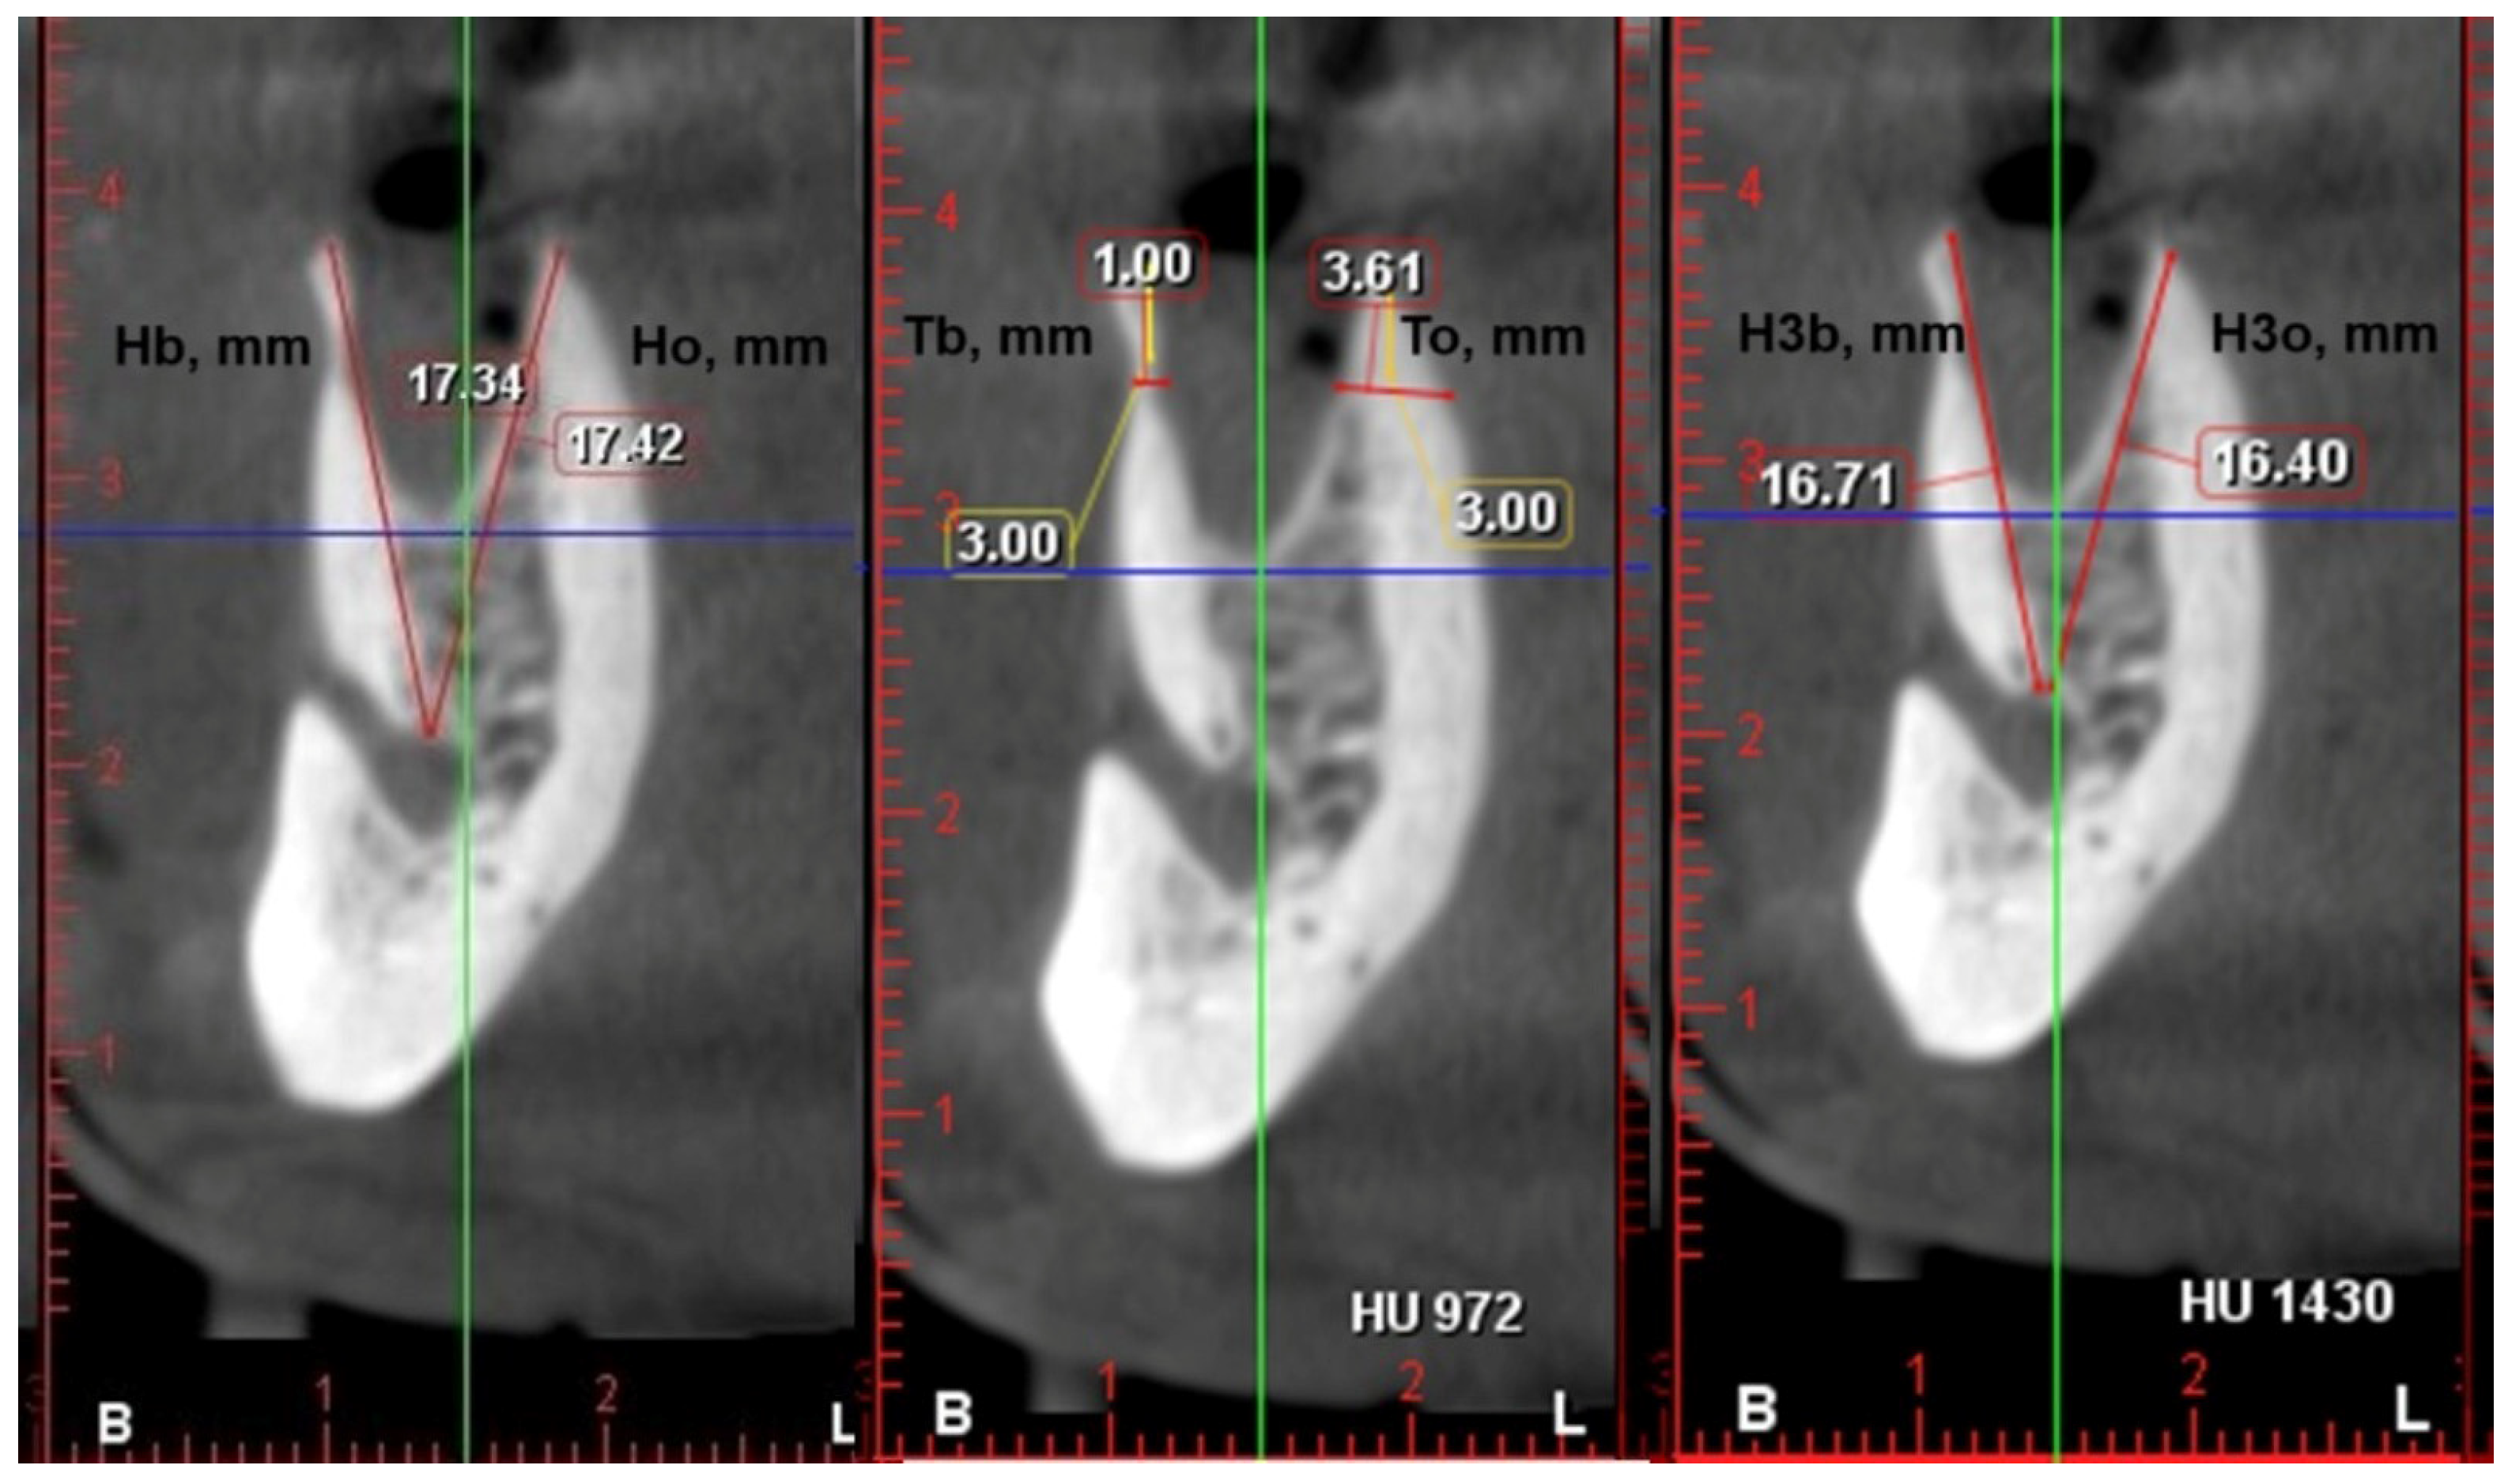

2.4. Radiological Examination